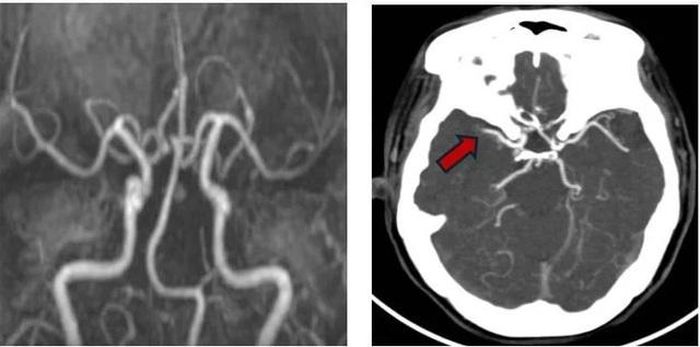

H́nh ảnh mạch máu đă tái thông trước đó với thuốc tiệu sợi huyết (H́nh A) và tái tắc do huyết khối mới – Rung nhĩ (H́nh B – mũi tên đỏ). Ảnh: BVCC

Lập tức, các bác sĩ tại Khoa Bệnh lư mạch máu năo kích hoạt quy tŕnh báo động đột quỵ nội viện. Chụp CT mạch máu năo khẩn ghi nhận h́nh ảnh tắc động mạch năo giữa bên phải – với h́nh ảnh huyết khối mới h́nh thành trong ḷng mạch máu. Không để thời gian trôi qua vô ích, người bệnh được chuyển thẳng vào đơn vị can thiệp mạch máu thần kinh. Tại đây, quy tŕnh can thiệp nội mạch được thực hiện khẩn trương và chính xác.